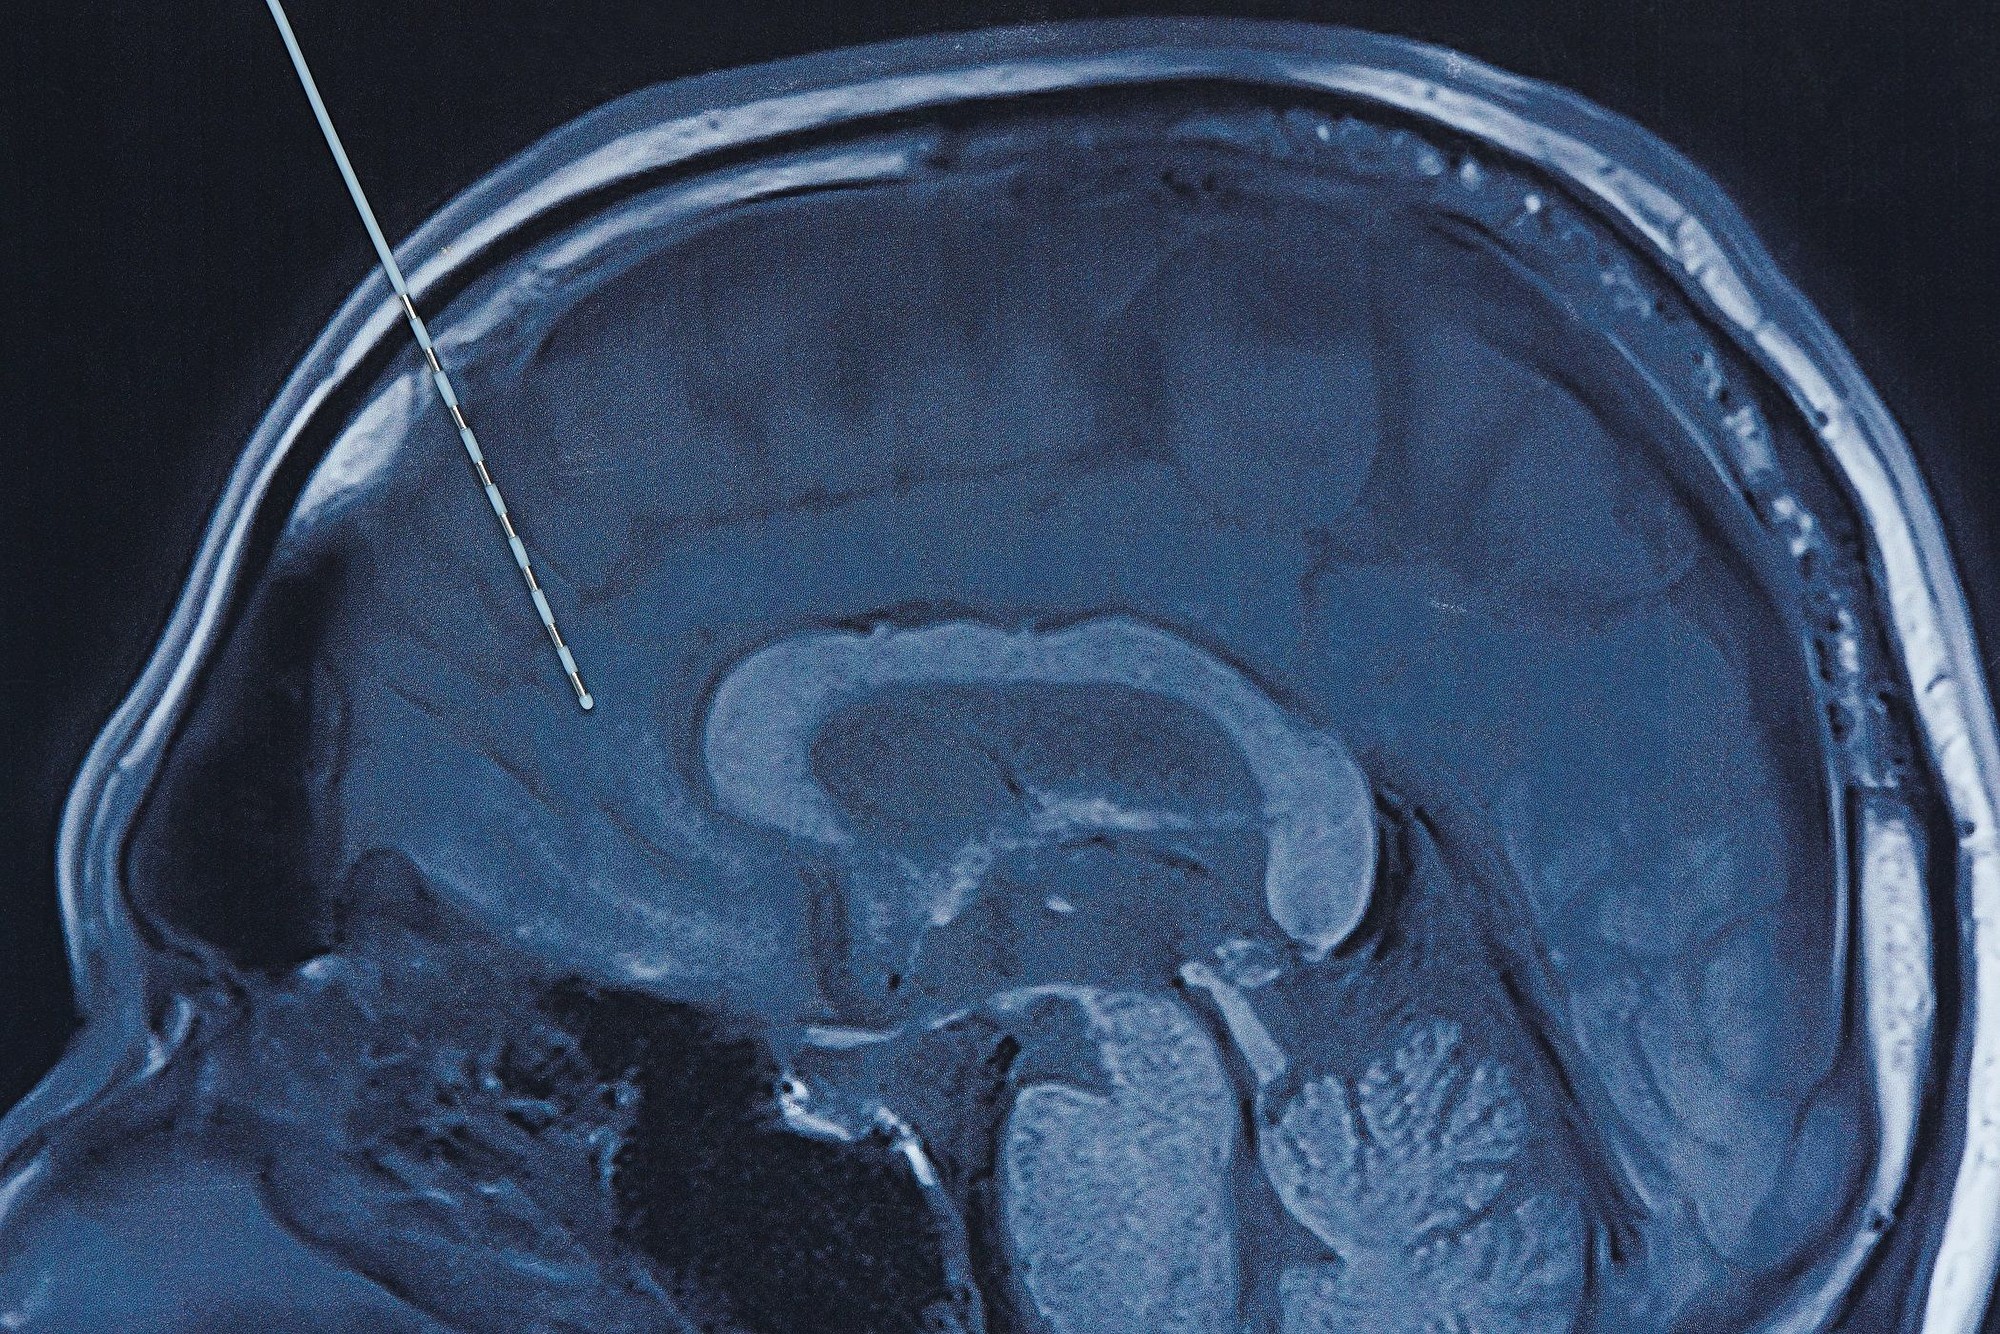

他們用麻醉昏迷的猴子進行實驗,使用比現有技術小得多的電極植入體,精確定位和匹配中央外側丘腦區域的位置和形狀。

據OneZero報導,威斯康辛大學麥迪遜分校(University of Wisconsin-Madison)的這項新研究中,發現大腦一個名為中央外側丘腦(central lateral thalamus)的特殊部位——位於腦幹上方,僅幾毫米大小的一個區域,對意識起到關鍵作用。